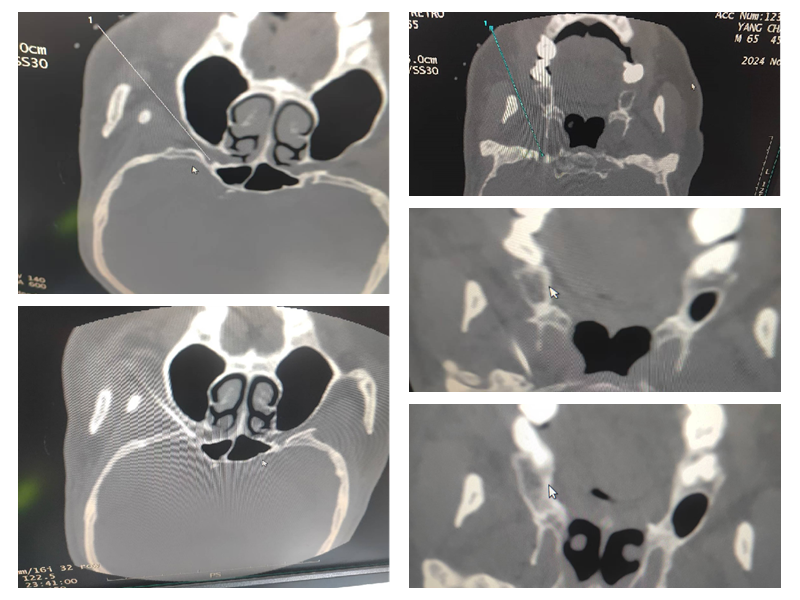

能完成该标准要求的绝大多数手术,包括选择性神经根阻滞技术、交感神经丛(干)介入医治技术、颅神经介入医治技术、神经射频调制技术、腰椎间盘介入医治技术、颈椎间盘介入医治技术、外周神经射频技术、脊髓电刺激、椎体成形术、硬膜外造影术、椎间盘造影术等。

颅神经介入医治技术